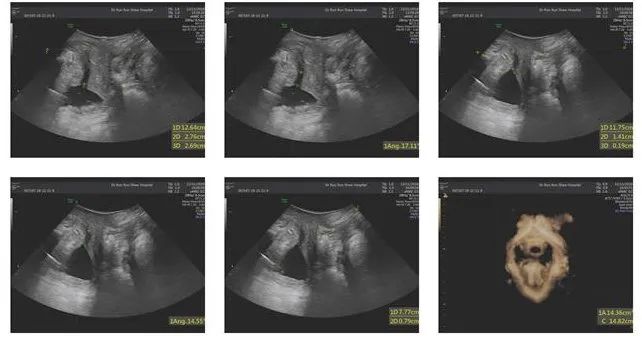

林女士的盆底彩超检查中,尿道内口的漏斗样开口,清晰可见。

康复科检查发现,林女士孕期BMI为28.3,产后4个月BMI为23.4,骨盆前倾、腹直肌分离-肚中3指,皮脂厚度31mm,1h尿垫试验12g(重度尿*禁失**),尿*禁失**生活质量问卷(IQOL)67分。

盆底肌表面肌电进一步提示,林女士快肌、慢肌及耐力均下降,盆底功能状态处于活动减弱型(松弛型)。

治疗4周后,林女士咳嗽漏尿症状明显减轻。复评结果显示BMI22.6,腹直肌分离脐中2指, 1h尿垫试验3g(中度尿*禁失**),尿*禁失**生活质量问卷(IQOL)84分,盆底快慢肌肌肉力量均有提高。